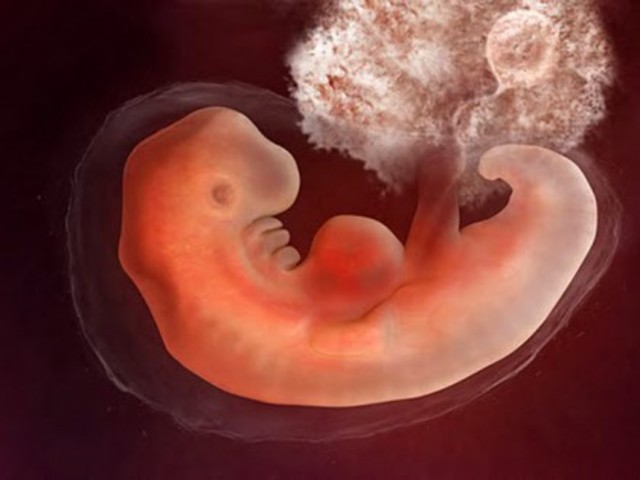

• Embryo

Embryo

The third through eighth week of gestation.